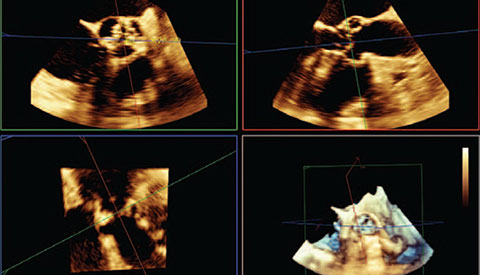

تساعدك القياسات الدقيقة للقوس الأورطي باستخدام البيانات ثلاثية الأبعاد في اختيار حجم الجهاز المناسب.

متابعة إجراءات التدخل وتقييمها من خلال الاتصالات الموسّعة بين أعضاء فرق طب القلب.

استخدام Live xPlane لتقييم النتائج. ما يتم عرضه هنا: عدم وجود تسريب في المنطقة المجاورة للصمام.